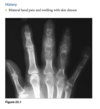

No history - hand pain

Anteroposterior and oblique views of the right hand (Figs. 2.27.1 and 2.27.2) show multiple metacarpal and phalangeal lesions with chondroid matrix, representing enchondromas and numer- ous hand and finger soft-tissue masses containing phleboliths. Maffucci syndrome (i.e., multiple en- chondromatosis with soft-tissue hemangiomas) transformation of enchondromas into chon- drosarcoma in patients with Maffucci syndrome.